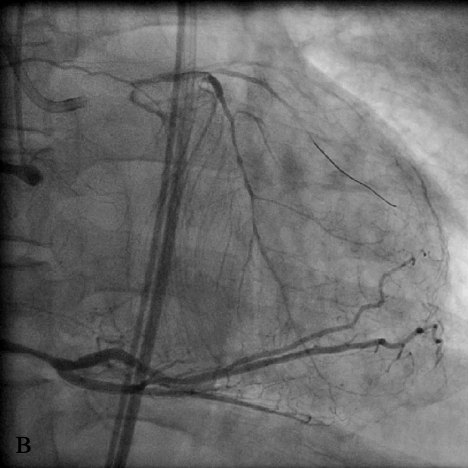

Коронарный проводник проведен за зону окклюзии, что подтверждено при выполнении коронарографии из ПКА (в), после чего выполнена баллонная ангиопластика окклюзированного ствола ЛКА (г). При контрольной коронарографии система ЛКА заполняется антеградно (д).